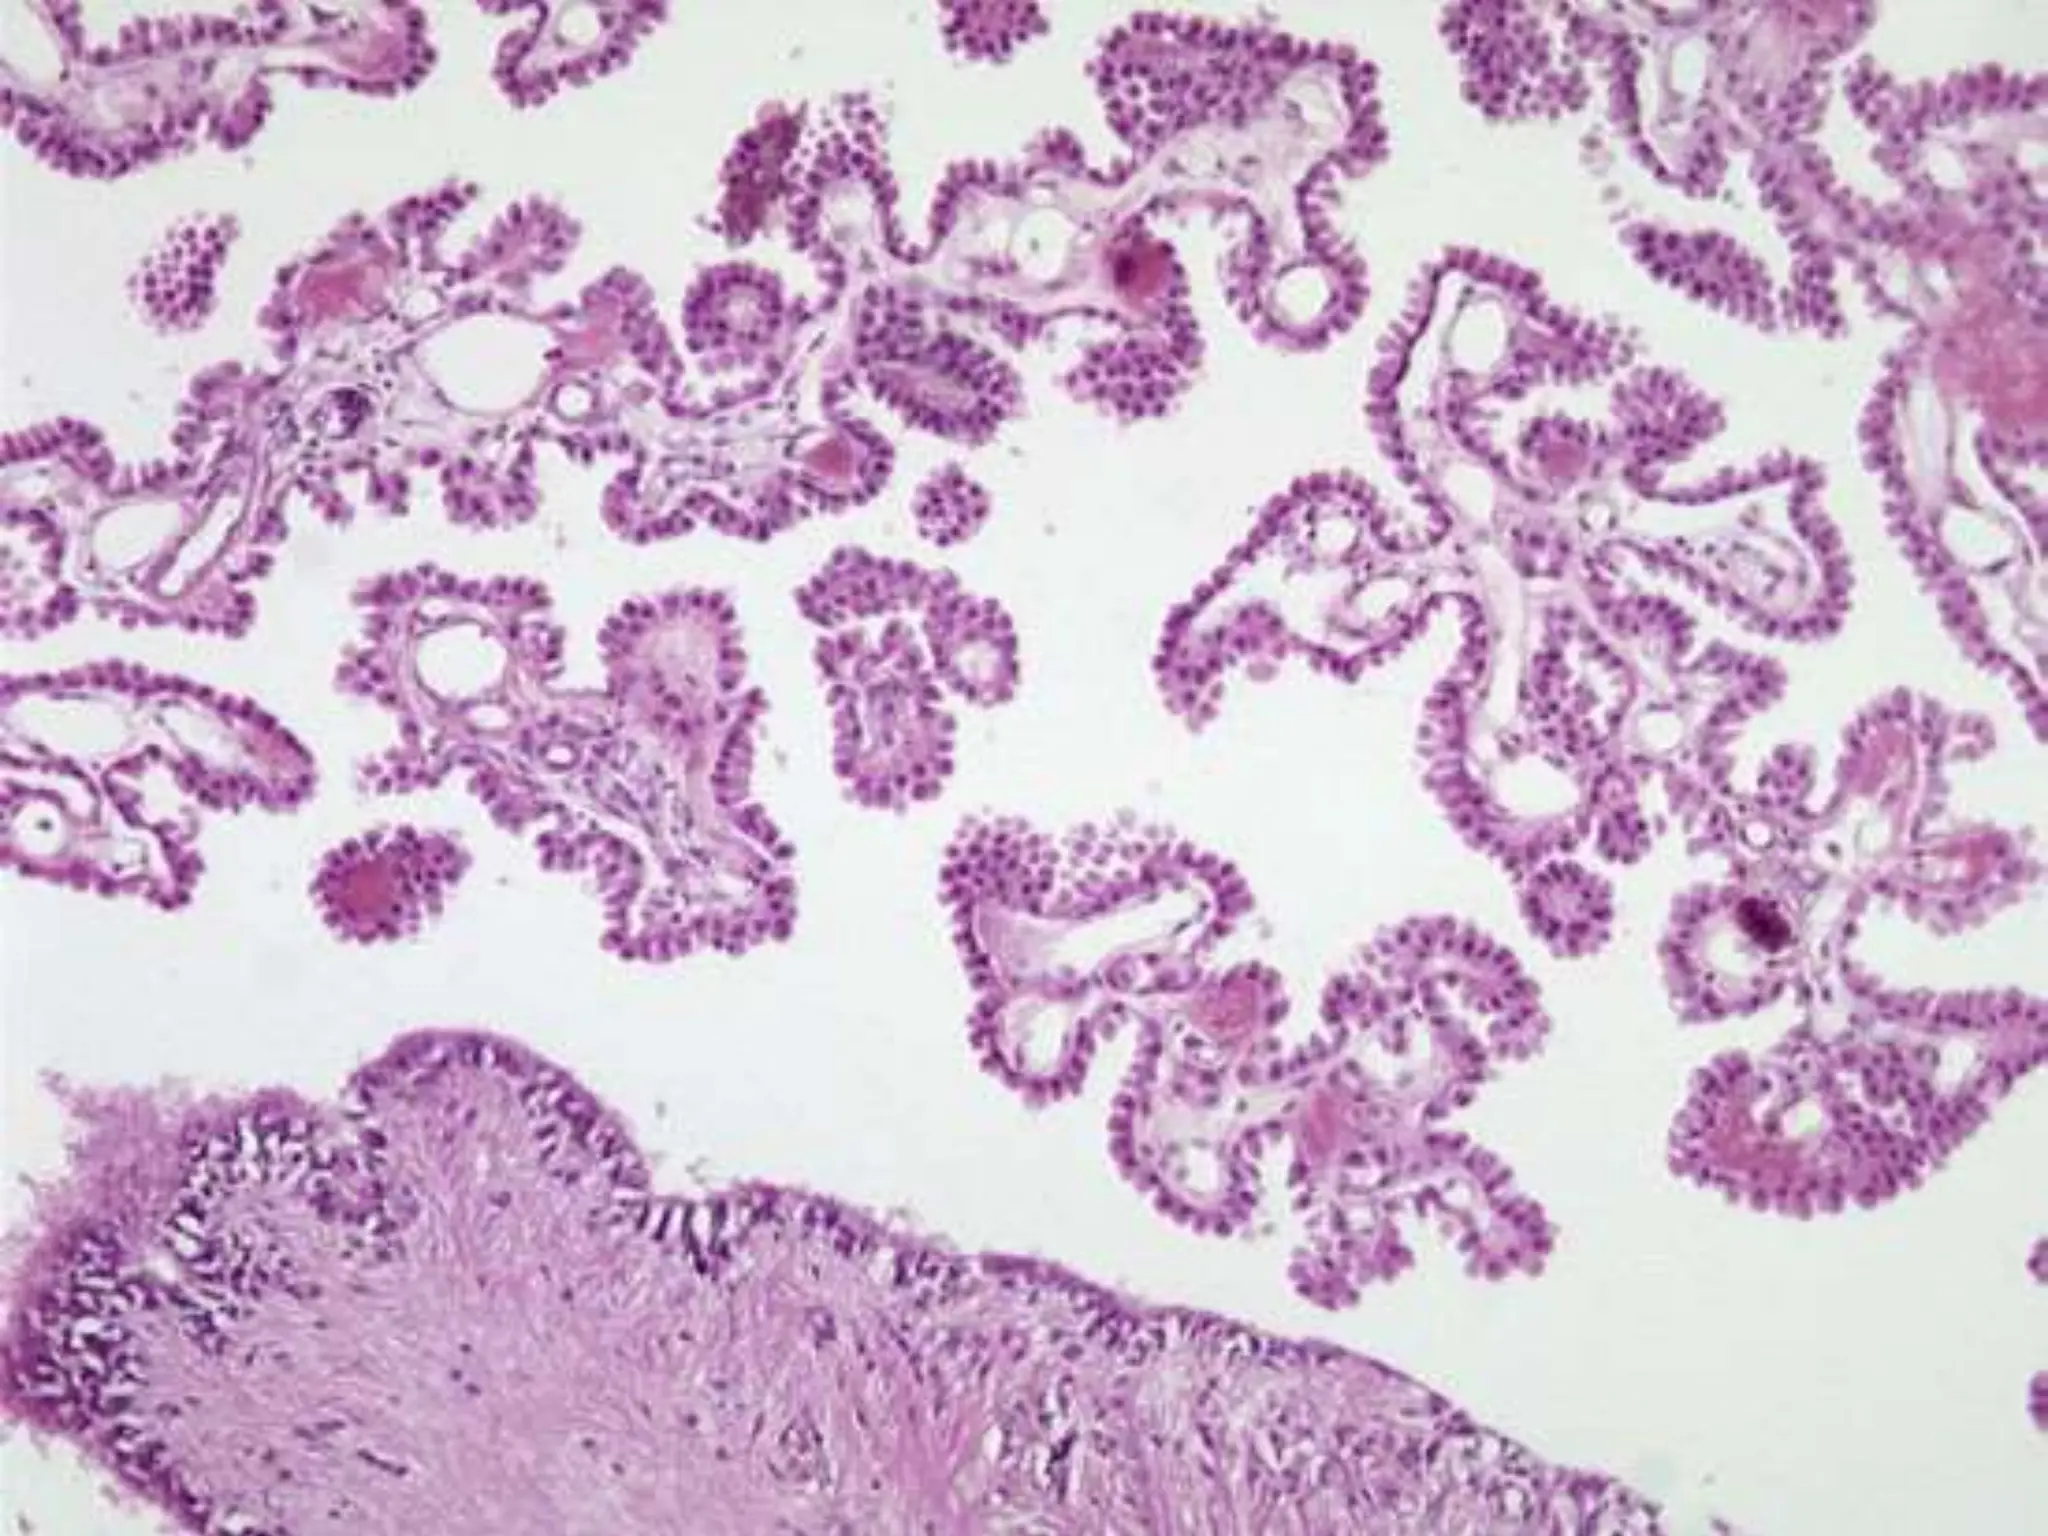

EPENDYMOMA

 1st two decades  4th

ventricle

 Adults  spinal cord,

common in

neurofibromatosis 2.

 C/F: obstructive

hydrocephalus

 Genetics: spinal type – NF2

gene alterations on chr 22.

 WHO grade II/IV

 Gross: Solid, papillary

masses extending from floor

of IV ventricle or spinal cord.

 Tumor cells form gland

like round structures 

rosettes or elongated

structures  canals

 As perivascular

pseudorosettes  cells

around vessels with

intervening zone of

GFAP +ve thin

ependymal processes

directed toward wall of

vessel.

EPENDYMOMA  1st twodecades  4th ventricle  Adults  spinal cord, common in neurofibromatosis 2.  C/F: obstructive hydrocephalus  Genetics: spinal type – NF2 gene alterations on chr 22.  WHO grade II/IV  Gross: Solid, papillary masses extending from floor of IV ventricle or spinal cord.

• 53.

EPENDYMOMA  Tumor cellsform gland like round structures  rosettes or elongated structures  canals  As perivascular pseudorosettes  cells around vessels with intervening zone of GFAP +ve thin ependymal processes directed toward wall of vessel.